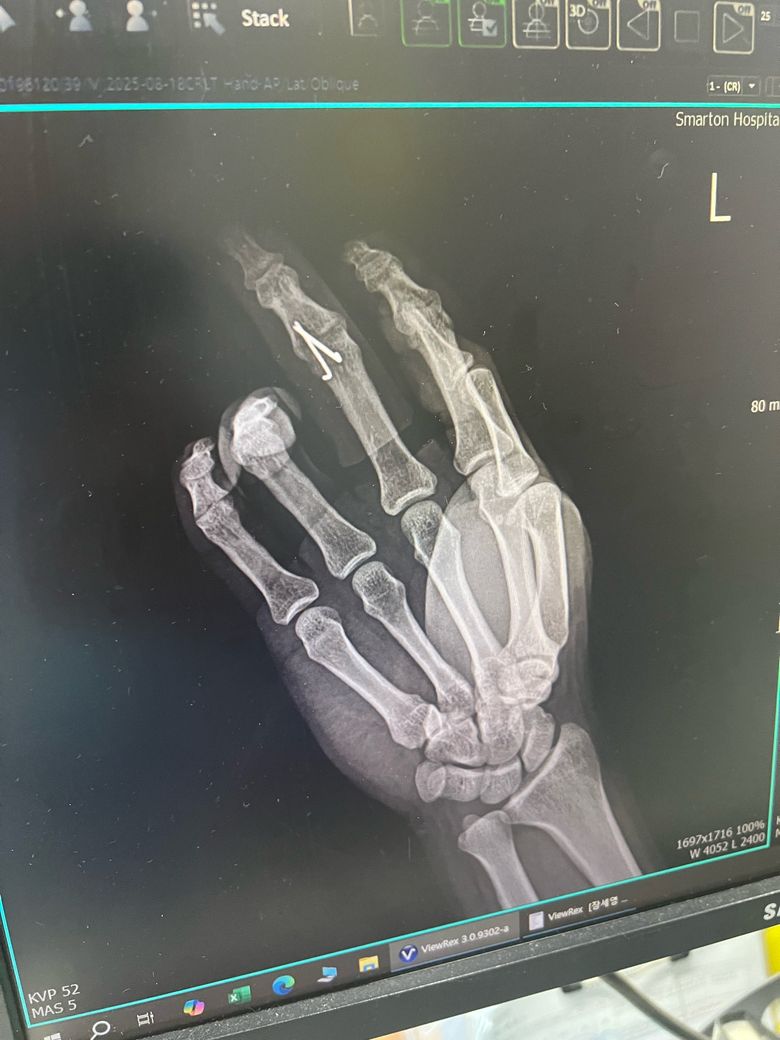

중지 골절 수술 후 운동을 언제부터 할수 있을까여

• 1번 째 사진